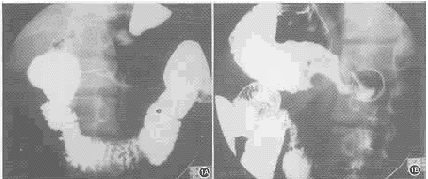

胃穿孔自然闭合一例

本文报道1例胃穿孔自然闭合10年后影像学检查表现 ......